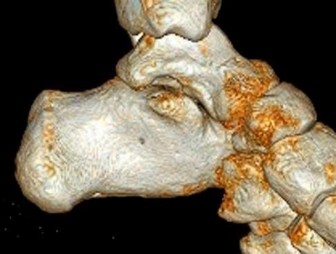

A 30-year-old female sustains a midfoot injury after falling from a horse. Radiographs demonstrate diastasis between the bases of the 1st and 2nd metatarsals. In a normal anatomic state, the native Lisfranc ligament originates and inserts on which two bony structures?

Correct Answer: Lateral aspect of the medial cuneiform to the medial aspect of the base of the 2nd metatarsal

Explanation:

The Lisfranc ligament is a stout, obliquely oriented intra-articular ligament that acts as the primary stabilizer of the second tarsometatarsal joint complex. It connects the lateral aspect of the medial cuneiform to the medial aspect of the base of the second metatarsal. Importantly, there is no direct ligamentous connection between the bases of the first and second metatarsals.